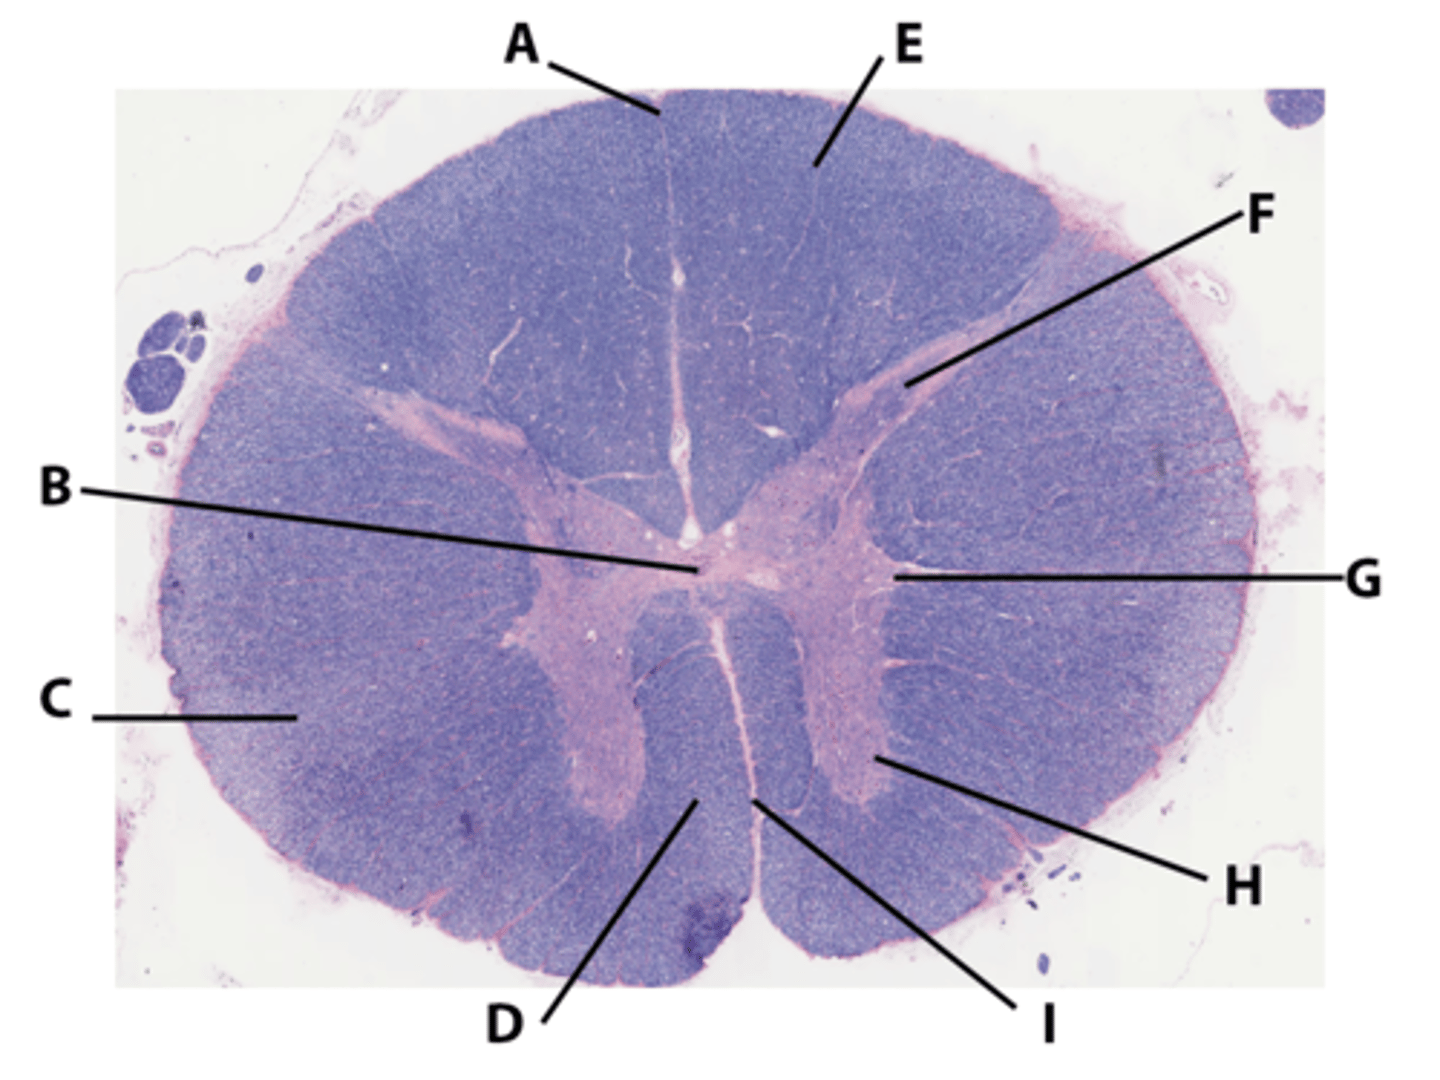

Gray matter

Posterior horn

Anterior horn

Lateral horn

G

Gray commissure

gray matter around this structure

Central canal

White matter

Posterior funiculus

Green

Anterior funiculus

Yellow

Lateral funiculus

Red

Posterior median sulcus

green

Anterior median fissure

red